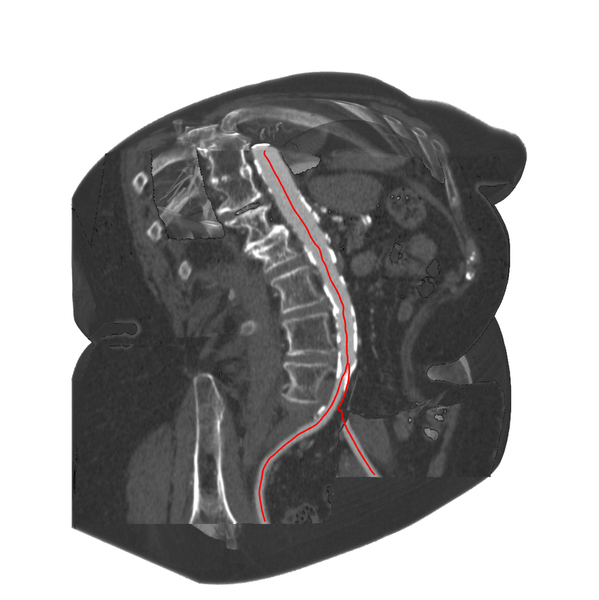

Result image : CSR applied to a medical volume data set of the bifurcation of the human abdominal aorta.Publication

This image has been taken from the following publication:| 2013 | ||

Thomas Auzinger, Gabriel Mistelbauer, Ivan Baclija, Rüdiger Schernthaner, Arnold Köchl, Michael Wimmer , Eduard Gröller , Eduard Gröller , Stefan Bruckner , Stefan Bruckner Vessel Visualization using Curved Surface Reformation IEEE Transactions on Visualization and Computer Graphics (Proceedings of IEEE Scientific Visualization 2013), 19(12):2858-2867, December 2013. [  Paper] Paper] |